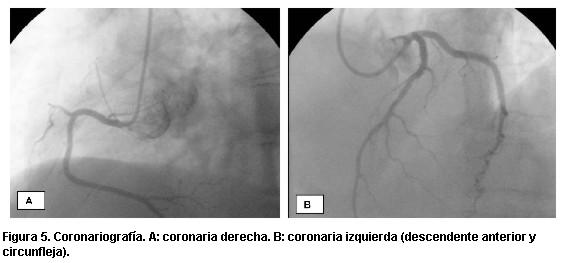

Figura 4. Ventriculografía. A: imagen en diástole. B: imagen en sístole.

Presentamos un caso clínico en el que se consideró como posible diagnóstico la miocardiopatía de takotsubo. Se trata de una paciente de 64 años, hipertensa, que consulta en emergencia por angor de reposo, prolongado, asociado a situación de estrés psíquico. Del examen físico del ingreso se destaca: paciente lúcida, eupneica, tolera el decúbito, bien hidratada y perfundida. Examen cardiovascular: ritmo regular de 70 cpm, ruidos bien golpeados, silencios libres, presión arterial 140/90 mmHg. Examen pleuropulmonar: buena entrada de aire bilateral, no estertores. En el electrocardiograma (ECG) del ingreso (figura 1) se objetivaba taquicardia sinusal de 110 cpm, P y PR normales, eje a aproximadamente -40 grados, ondas Q patológicas en cara anteroseptal, ascenso del segmento ST de V2 a V4, QT 0,38 s. Se administran nitritos sublinguales, cede el dolor y renivela el segmento ST (figura 2). El test de troponinas fue negativo. La paciente fue dada de alta a domicilio con ácido acetilsalicílico (AAS), betabloqueantes y pase a cardiólogo. A los cuatro días consulta por nuevo episodio anginoso. El ECG de ese momento muestra elementos sugestivos de isquemia subepicárdica extensa (figura 3). El enzimograma cardíaco fue negativo. Se inició tratamiento en base a AAS, heparina de bajo peso moleculary nitroglicerina, con lo que cede el dolor. Se realizó un ecocardiograma que evidenció hipoquinesia apical y disminución leve de la fracción de eyección del ventrículo izquierdo. En la cineangiocoronariografía realizada de urgencia se informó ausencia de lesiones coronarias significativas; hipoquinesia severa anterior y apical (figuras 4 y 5). La paciente evolucionó asintomática. Se confirmó ecocardiográficamente la recuperación de la motilidad y función ventricular en el plazo de un mes